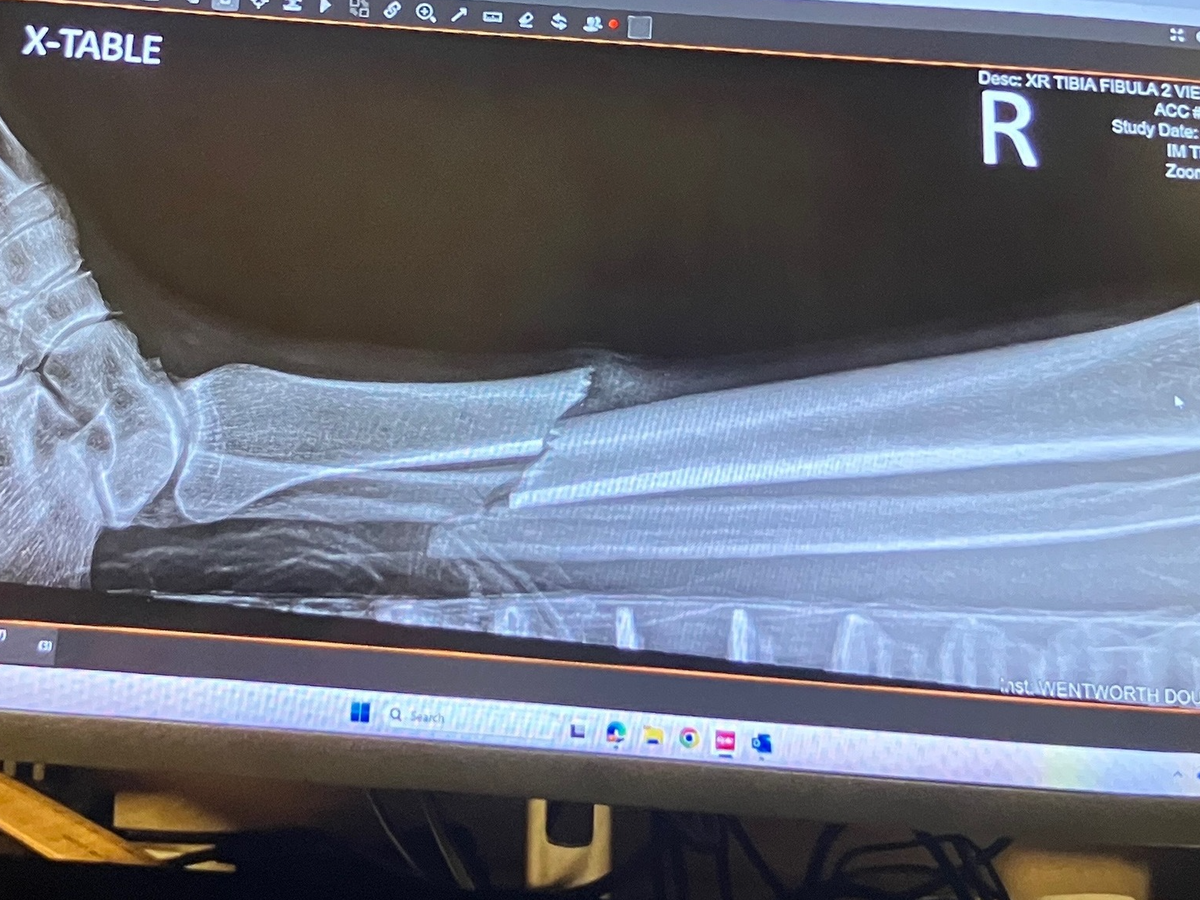

there i was, out on an epic early morning trail ride with a couple of stablemates, when one of their horses fired a hoof out and got me in the shin. i'm speculating the bugs were pissing her off and she didn't really know my horse. no sense getting mad about it, i'ts done. i actually quite like the mare. i knew instantly it was broken. after an initial 'fight' response by my horse, she got a grip and carried me back to the barn, like the wounded soldier i was. she's used to sidling up to our mounting block for me to dismount, so that wasn't weird for her. i swung my bad leg over her back, landing on my good one. with considerable assistance, i got into a car and was transported to the ER at Wentworth Douglass Hospital.

they called me a blessedly short time after arriving. it was an open wound so surgery had to be immediate. i had not eaten and drank only sparsely that morning so that was good, and there was a good leg doc available. damage control was going well. next thing i know, i'm sporting a titanium rod from knee to ankle with a screw at each end. i am SO grateful for modern medicine and good surgeons, not to mention my beloved barn family, who have been killing me with loving kindness and delicious food since coming home.